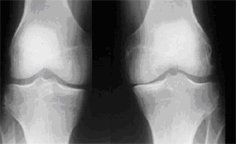

This will only show bone but it may be important to rule out any fractures (breaks) and also to see how the bones are positioned in relation to each other. Sometimes a 'stress X-ray' is done to assess the integrity of the collateral ligaments - the X-ray is taken while sideways pressure is applied to the knee.